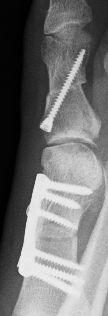

Roentgenbild  Roentgenbild von oben und von der Seite